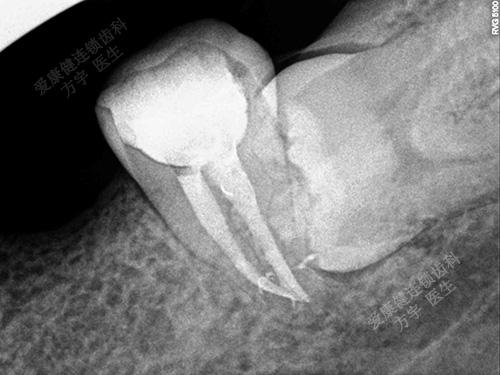

术后